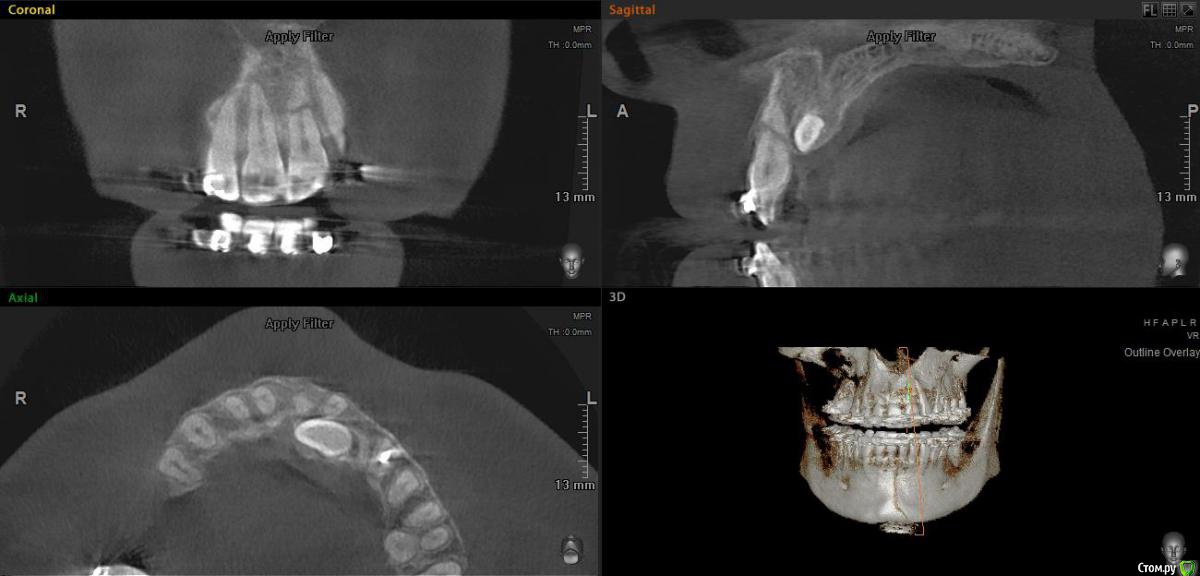

Паращук Роман Опубликовано 10 февраля, 2020 Поделиться Опубликовано 10 февраля, 2020 (изменено) На холод реагирует,в цвете не изменен. ЭОД,увы,нет возможности проверить.между снимками год разницы,периапикальных изменений не появилосьЯ бы посоветовал исключить зуб как опору для вытягивания клыка и всячески стараться его не двигать. Ниже аналогичный случай. Травма 20 лет назад. Цвет в норме,холодовой так же,подвижность поболее чем соседей. Обратите внимание как сработала пульпа! Так что все будет гуд! Изменено 10 февраля, 2020 пользователем Паращук Роман 1 Ссылка на комментарий